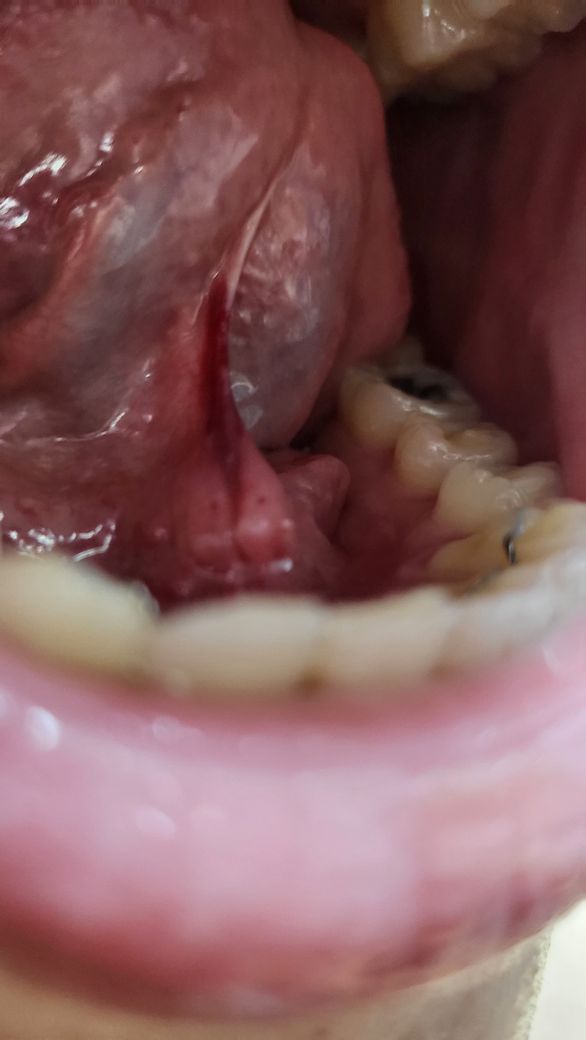

혀아래 힘줄 색깔 통증있는데 뭔가요?

지금 양치하던중 갑자기 아프길래 보니까 이러내요

멍든것 혹 피가고인것처럼 되어있고 통증이 신경쓰이는 정도로 있어요 크게 문제가 안된다면 병원은 안가고싶은데 갈 시간도 없어서

혀의 아래의 정맥이 지나가는 곳은 어두운 색을 띠고 있습니다.

정상적인 구조물이기 때문에 큰 문제가 되지는 않지만 걱정이 되신다면 치과에서 지세한 진료를 받아보세요.